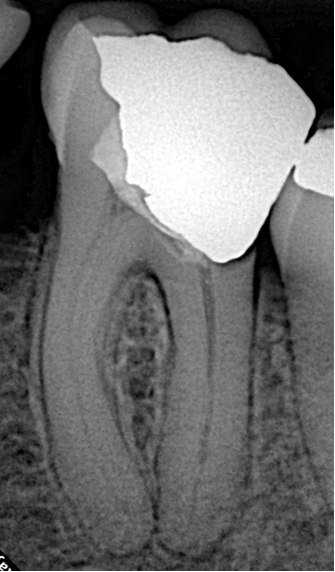

The patient was referred with a large radiolucent lesion surrounding the distal root of the crowned lower left first molar (#36). The periapical radiograph revealed substantial periapical pathology and pronounced curvature in the apical third of the root canal system. Such anatomy significantly increases the risk of procedural errors such as ledging, transportation, or instrument separation during shaping.

Diagnosis: Apical periodontitis with a massive distal root lesion.